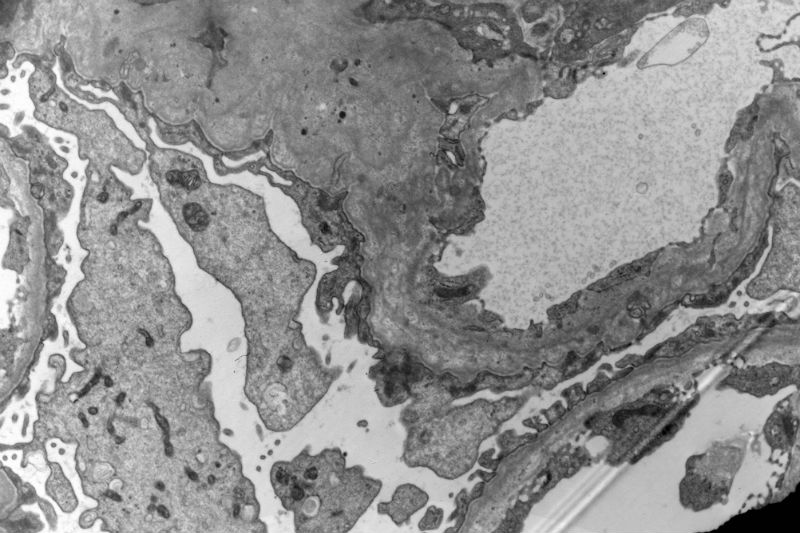

The patient has a long history of "chronic kidney disease". Initially, he did not tell the nephrologist that he started to have kidney disease decades ago. Given the characteristic ultrastructural changes, Alport's syndrome is suggested.

Yes, I agree with your observation that there are a lot of foamy cells. The most impressive change is the lamination or splitting of the glomerular basement membrane.